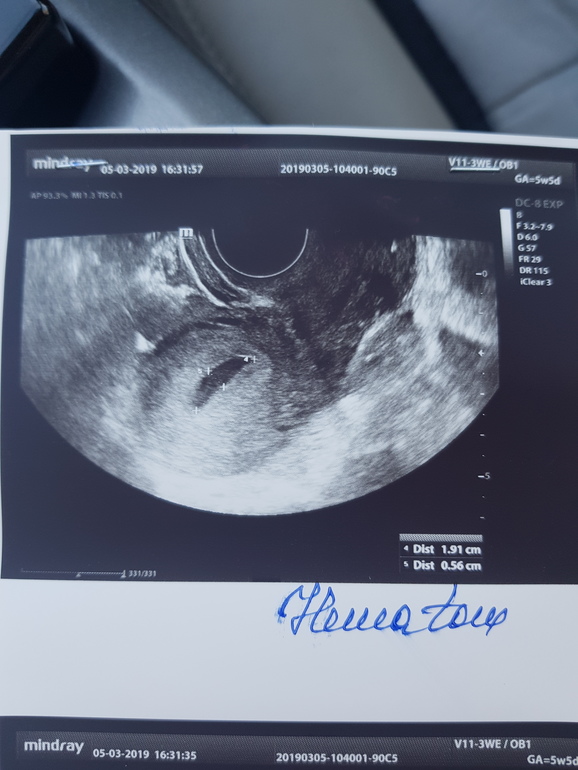

По месячным 5нед6дней, но овуляция была на неделю позже и срок меньше. Вчера была на узи, чтобы исключить внематочную. Нашли плодное яйцо 4,3 мм и большую гематому рядом 19,1 на 5,6 мм. И еще кисту желтого тела 5 см. Узист напугала страшно. Угроза выкидыша, полный покой, никаких каблуков и секса. Я отправила узи врачу, сказал подходить в четверг, до четверга ничего не предпринимать.

Вот фото узи

Гематома